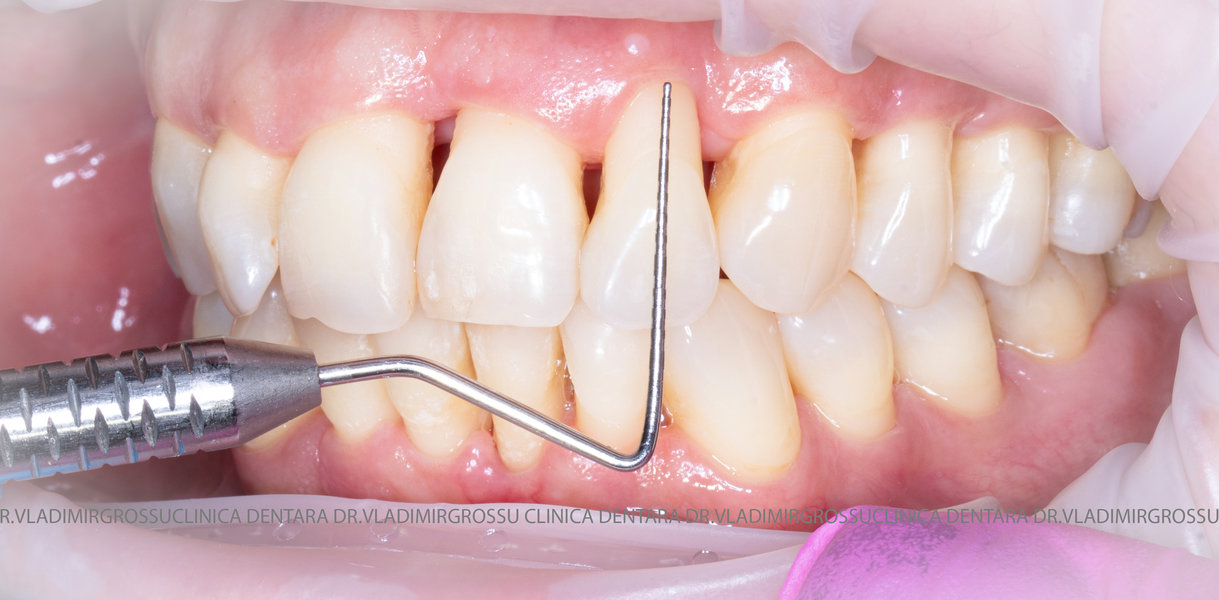

Aditia gingivală este o procedură chirurgicală ce corectează diverse probleme estetice și funcționale, cum ar fi recesiunea gingivală. În implantologia modernă, aditia de țesut moale este utilizată aproape în fiecare intervenție de inserție a implantului dentar pentru a asigura un aspect estetic natural și o bună integrare a implantului în cavitatea bucală.